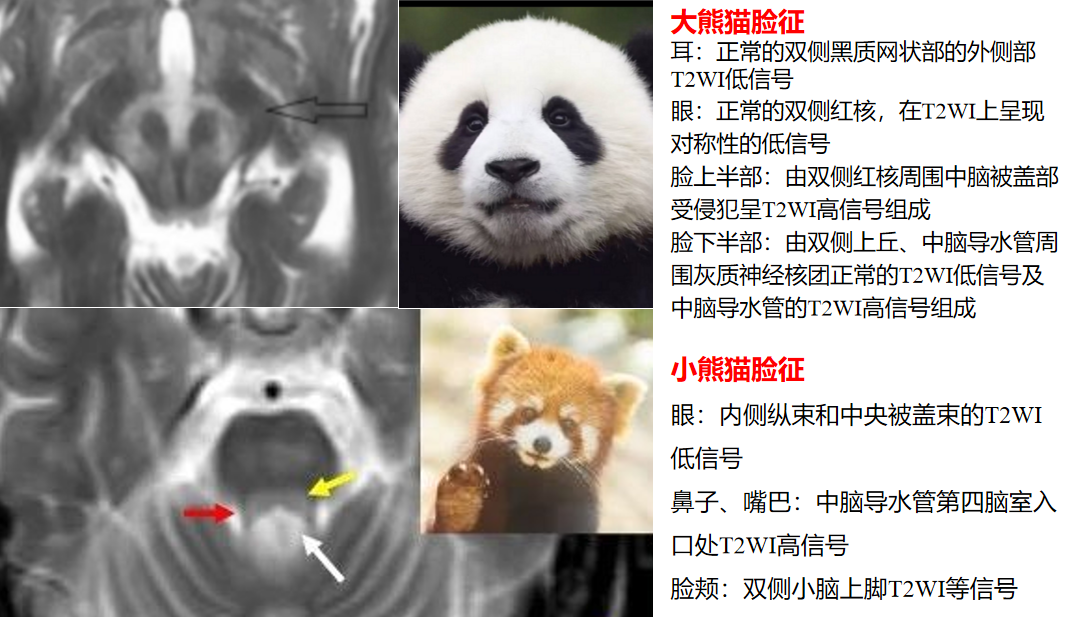

“熊猫脸征”常见于Wilson病,分为“大熊猫脸征”和“小熊猫脸征”,是该病在脑干结构选择易损性的影像学表现。T2WI图像上“大熊猫脸征”出现在中脑层面,红核为对称性低信号,构成熊猫的眼睛,而红核以外的中脑顶盖结构高信号构成熊猫的上半身白色轮廓,侧面的黑质网状部的正常信号构成耳朵,上丘低信号构成嘴巴。“小熊猫脸征”出现在脑桥被盖层面,内侧纵束和中央被盖束呈低信号构成小熊猫眼睛,导水管开口进入第四脑室的高信号构成鼻子和嘴。需要注意的是“熊猫脸征”并非Wilson病脑部MRI特征性表现,其他疾病如Leigh病、脑干梗死、EB病毒相关性脑炎、甲硝唑脑病、甲醇中毒及缺血缺氧性脑病等也可出现该征象。